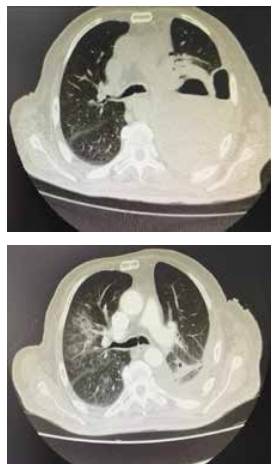

El paciente reingresó al servicio de urgencias a los 15 días por fiebre y dificultad respiratoria, y se diagnosticó un choque séptico, por lo que se realizó una TC de tórax que mostró una colección compleja en el hemitórax izquierdo, ocupando casi toda la extensión del hemitórax, de paredes gruesas (figura 1). Ante los hallazgos de empiema recurrente y en fase organizada, se plantea un nuevo procedimiento quirúrgico, no obstante, siendo un paciente que se encontraba en condición de fragilidad, se decide cambiar de estrategia terapéutica, realizando una toracostomía abierta con resección parcial del séptimo y octavo arcos costales.